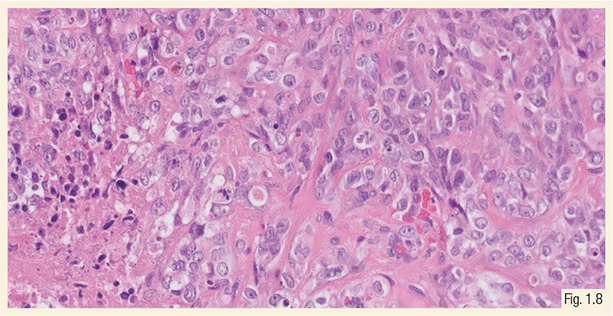

介质润滑镜中超细胞圆细胞分量百分比决定等级: > 5%被视为高等级